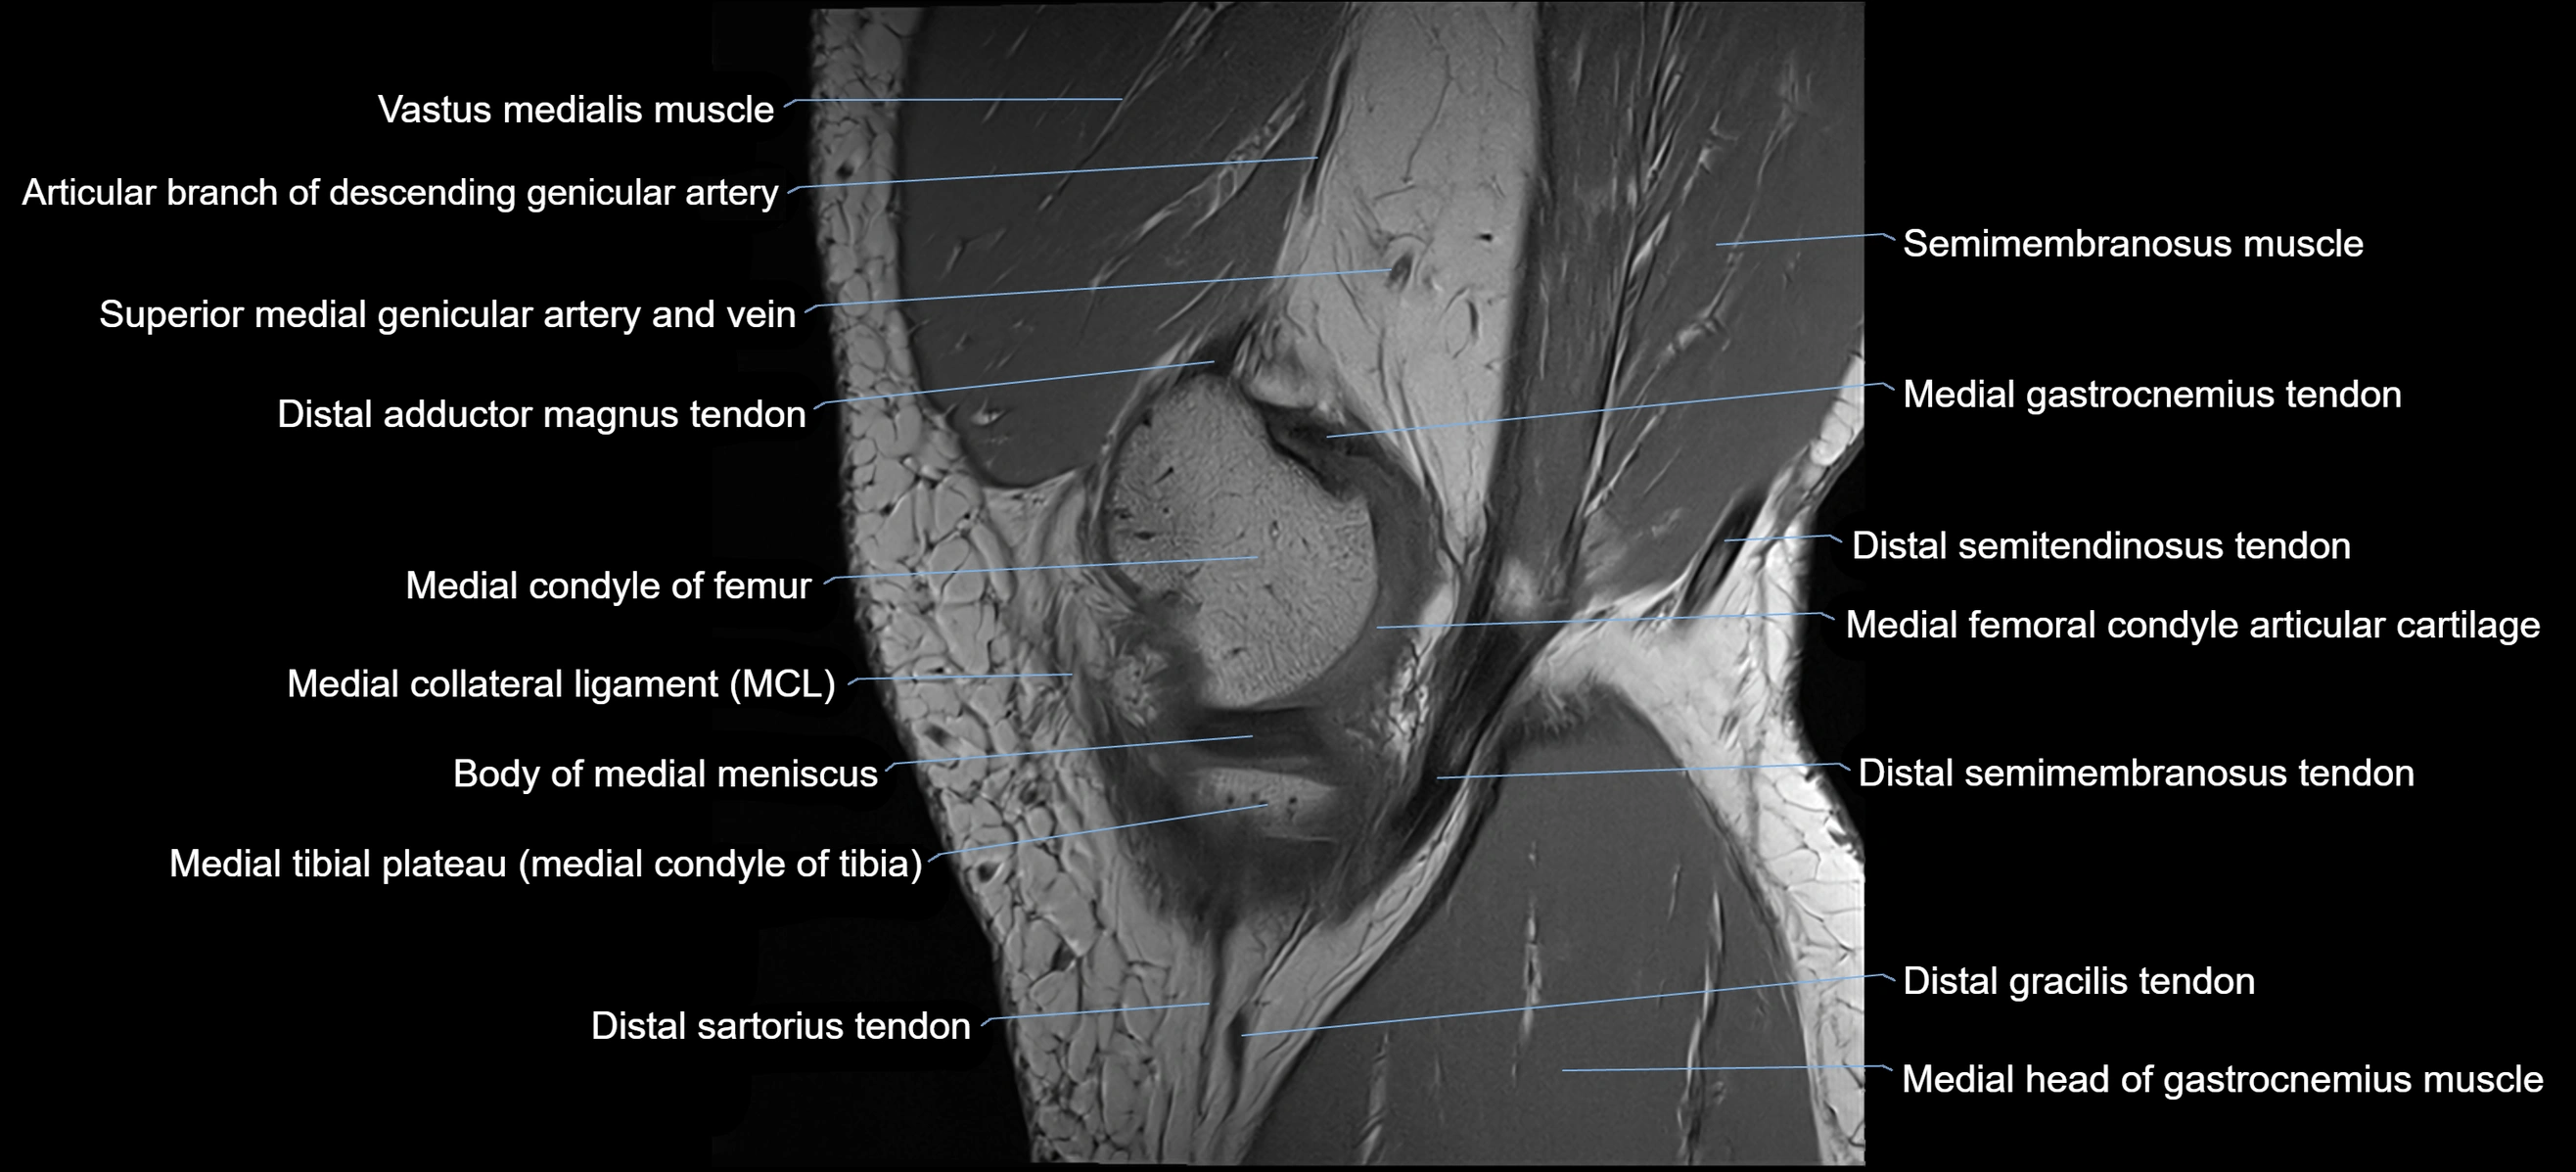

- Body of medial meniscus

- Distal adductor magnus tendon

- Medial collateral ligament

- Medial condyle of femur

- Medial condyle of tibia

- Medial gastrocnemius tendon

- Medial head of gastrocnemius muscle

- Medial tibial plateau

- Sartorius muscle

- Sartorius tendon (Distal)

- Semimembranosus muscle

- Superior medial genicular artery